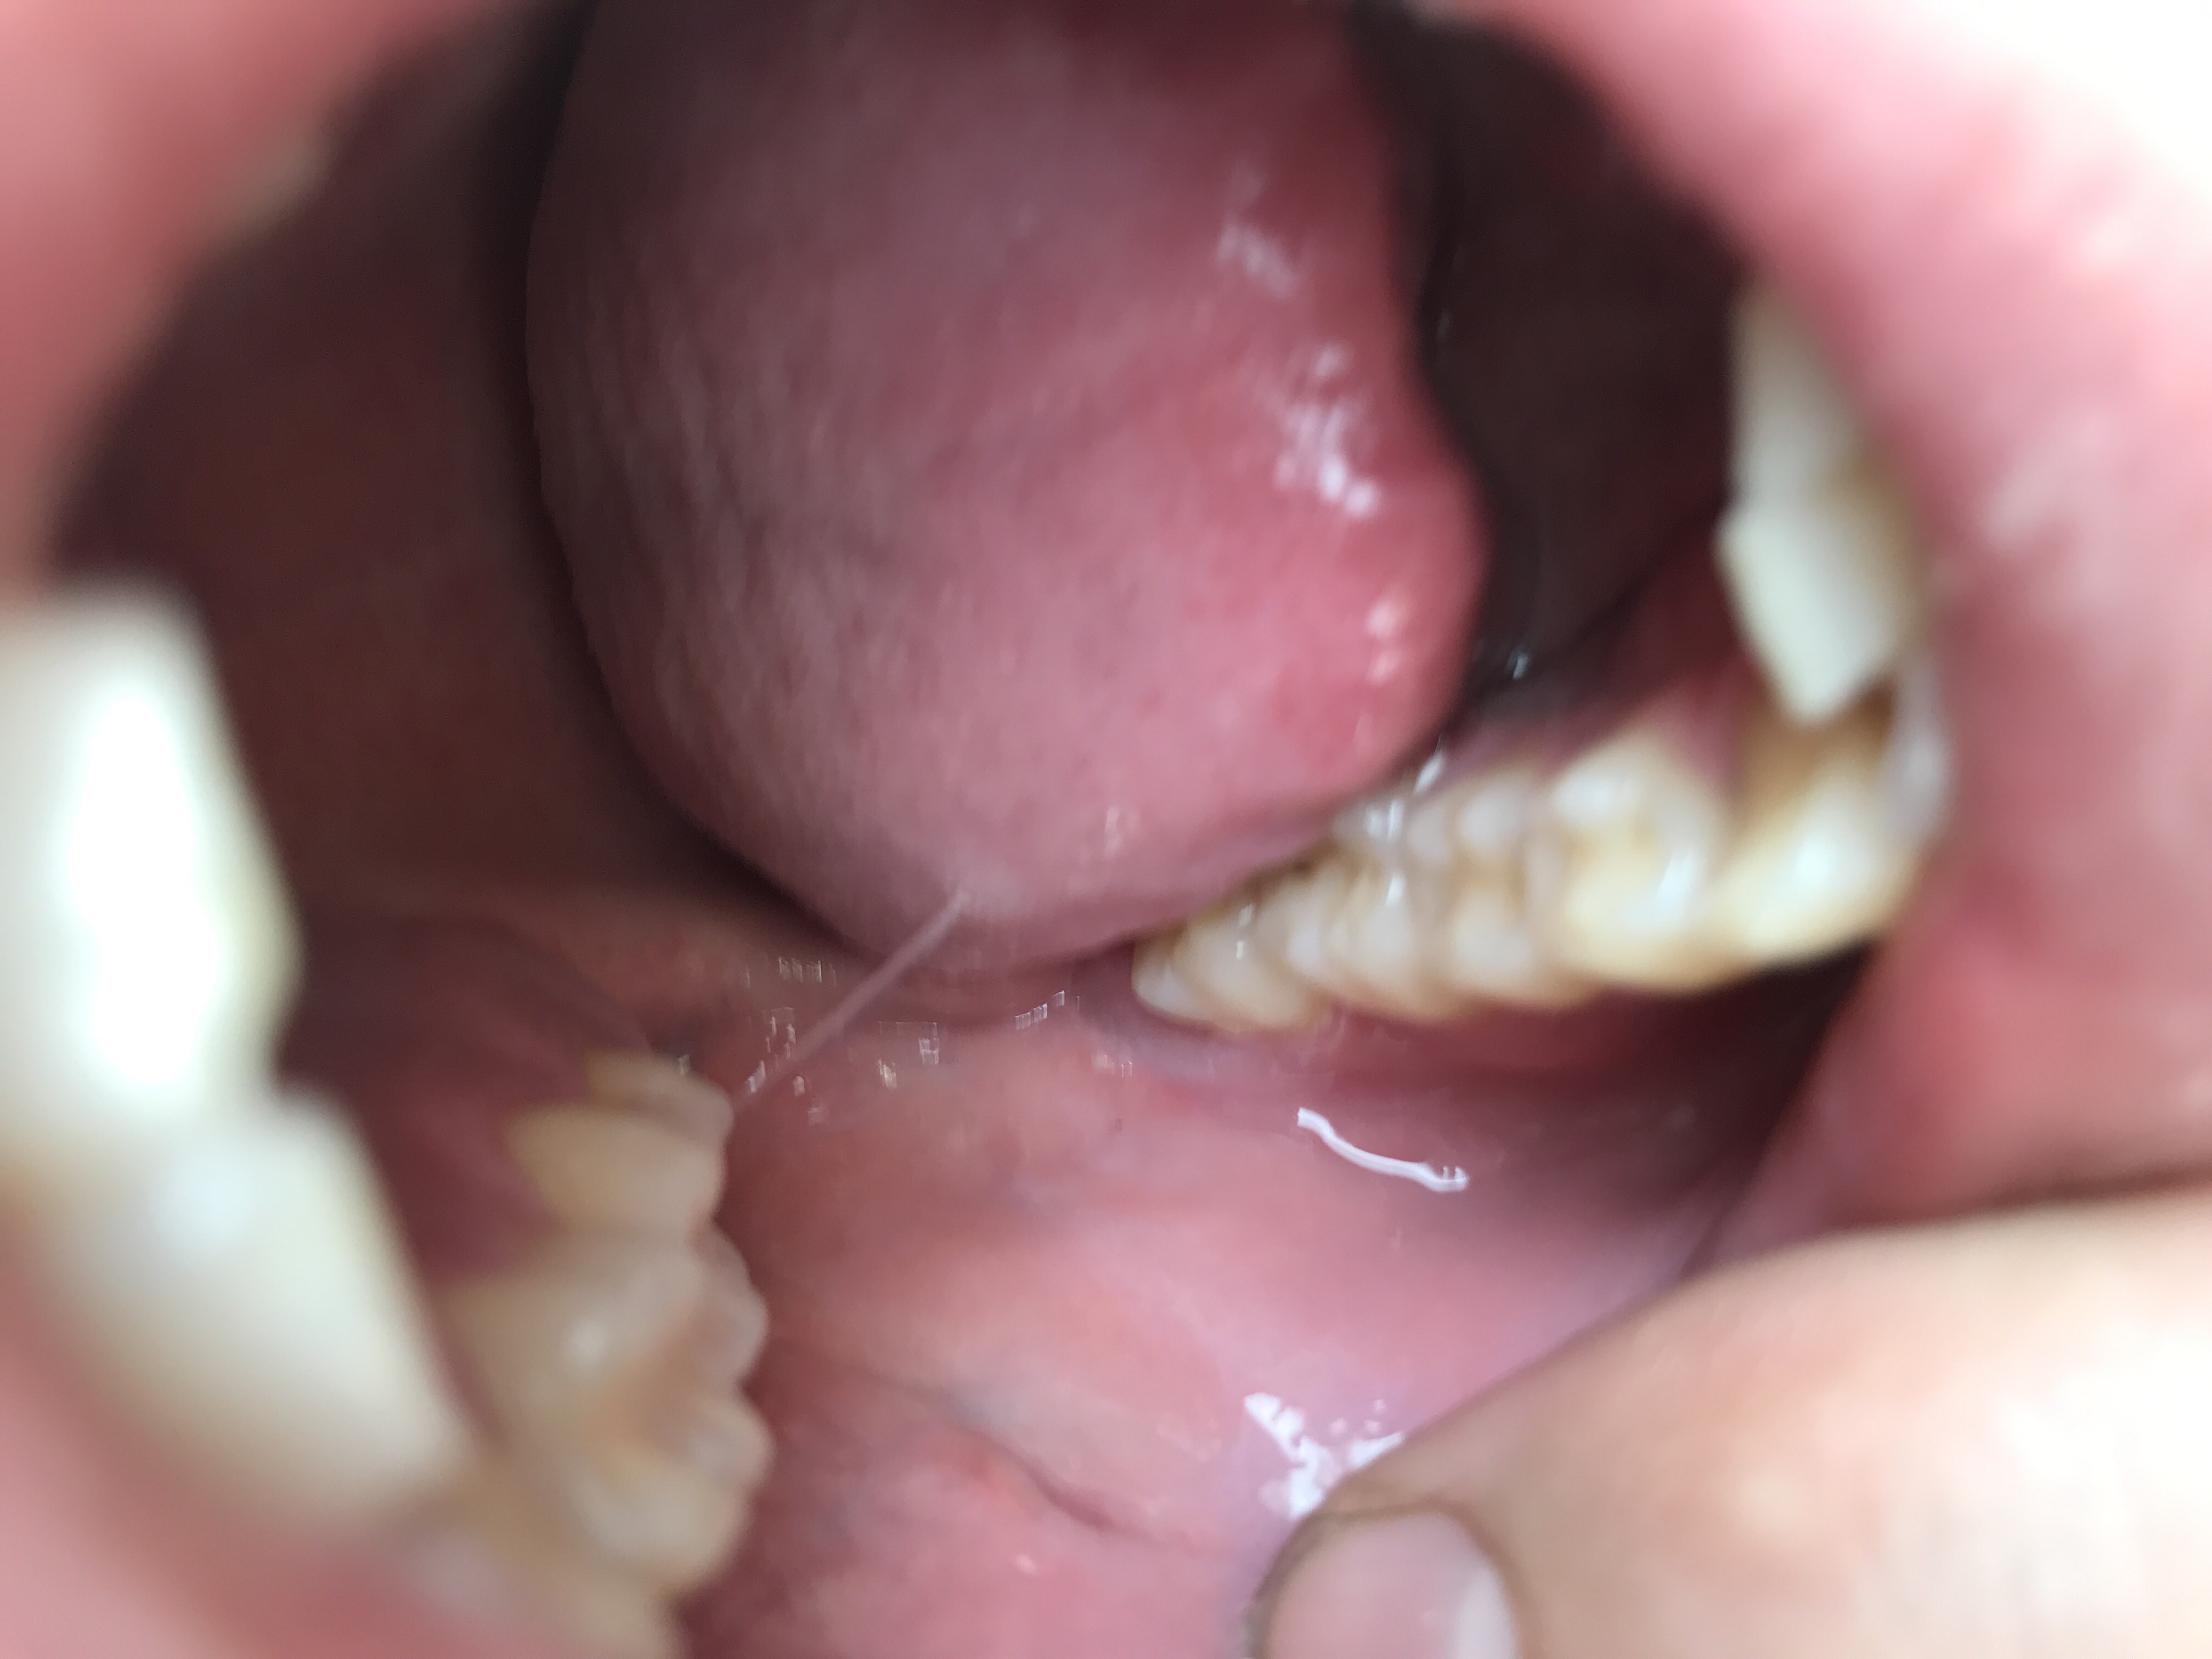

Op de foto is het nu een blauwige streep en soms een witten vlek met een lijn er aan het veranderd constant verder zag ik dat het linae alba of lichus planus is maar die symptomen heb ik niet